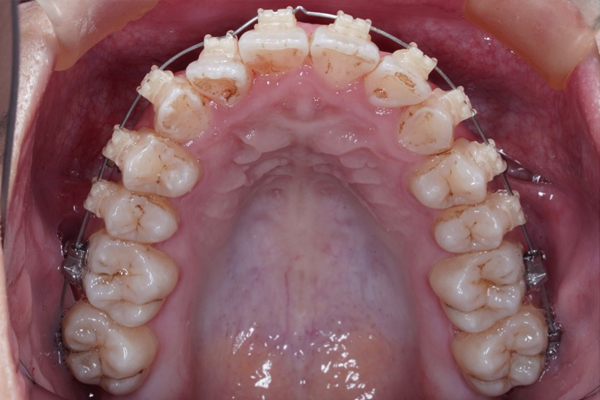

【3ヶ月経過の変化】

• 前歯の重なりが減り、アーチが広がってきました。

• 下の歯はほとんど並びました。

【治療方針詳細】

• ワイヤー矯正治療

• 非抜歯矯正治療

• インプラントアンカーにより歯を後ろに動かします。